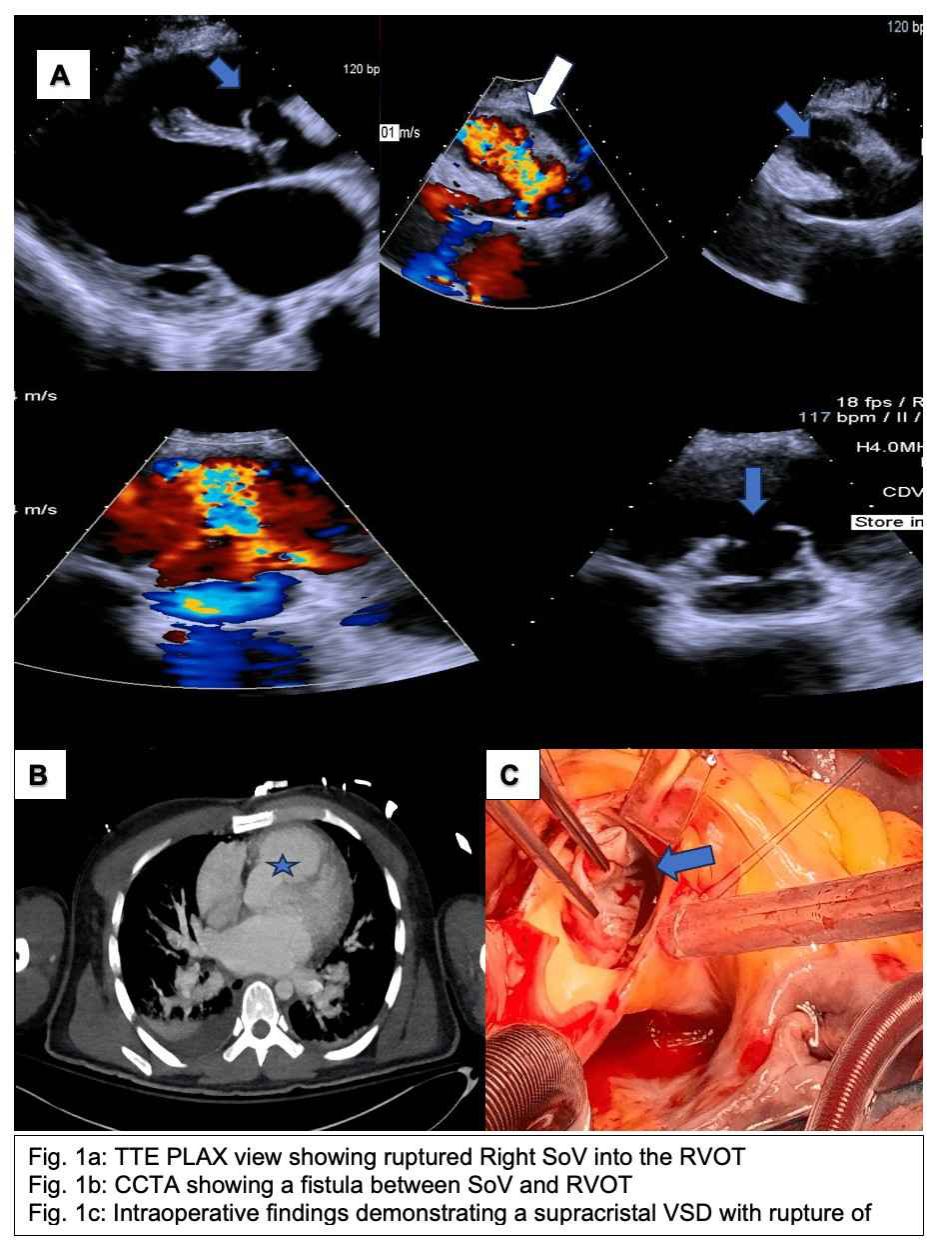

CASE PRESENTATION:A 27-year-old male with a past medical history significant for a VSD (diagnosed at childhood but lost to follow up at 18 years of age) who was admitted to the intensive care unit for management of undifferentiated shock, acute renal failure and acute liver failure. Upon initial evaluation, vital signs showed blood pressure of 130/34 mmHg, heart rate 118 bpm, SpO2 100% on 3L NC. An emergent transthoracic echocardiogram with color doppler showed unrestricted left to right flow from the RSoV to RVOT in systole and diastole with concern for ruptured SoV aneurysm. A non-contrast CT scan of the chest also showed a dilated pulmonary trunk with a connection between the SoV and RVOT. Patient underwent primary closure of the VSD, as well as a patch repair of a large fistula between R sinus of Valsalva and RVOT. Patient steadily improved with normalization of renal function and hepatic function. DISCUSSION: Aneurysm of the sinus of Valsalva (SoV) is a rare acquired or congenital anomaly predominantly affecting the right and the noncoronary sinuses, with an estimated prevalence of 0.09% of the population. Most sinus of Valsalva aneurysms arise from the right or the noncoronary sinuses. The most common site of rupture of SOV aneurysm is into the right ventricle followed by right atrium, left ventricle, and the left atrium. Hemodynamically, the flow through VSD produces Venturi effect “windsock effect. This left to right shunt caused by the supracristal VSD weakens the elastic lamina of the aortic sinus creating the SOV aneurysm. Overtime due to continuous negative pressure a SOVA develops on the right aortic root, which can rupture into the right ventricular outflow tract as seen in our case. CONCLUSION: Sinus of Valsalva aneurysm rupture is a rare but potentially fatal complication and should be considered on the differential in a young individual with underlying sVSD presenting with hemodynamic collapse.